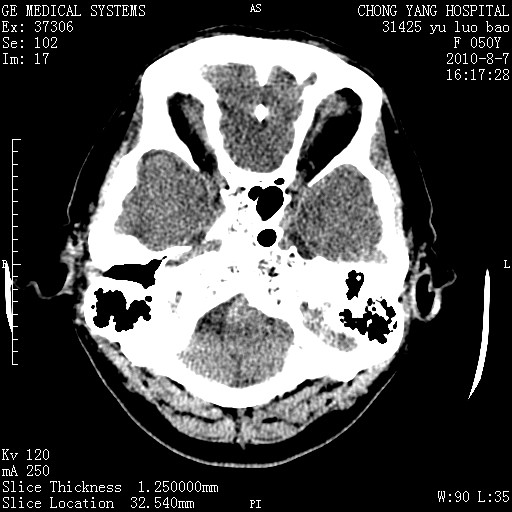

标题: CT28285:听力下降一年,头昏。 [打印本页]

标题: CT28285:听力下降一年,头昏。

右侧桥小脑角区占位--听神经瘤,建议增强或mri检查。

右侧桥小脑角去等密度占位,右侧内听道扩大、骨质吸收,考虑:右侧听神经瘤,建议增强检查。

右侧内听道扩大、骨质吸收,中脑受压左移,考虑:右侧听神经瘤,建议增强检查。支持!

右侧桥小脑角区等密度占位,内耳道扩大,听神经瘤